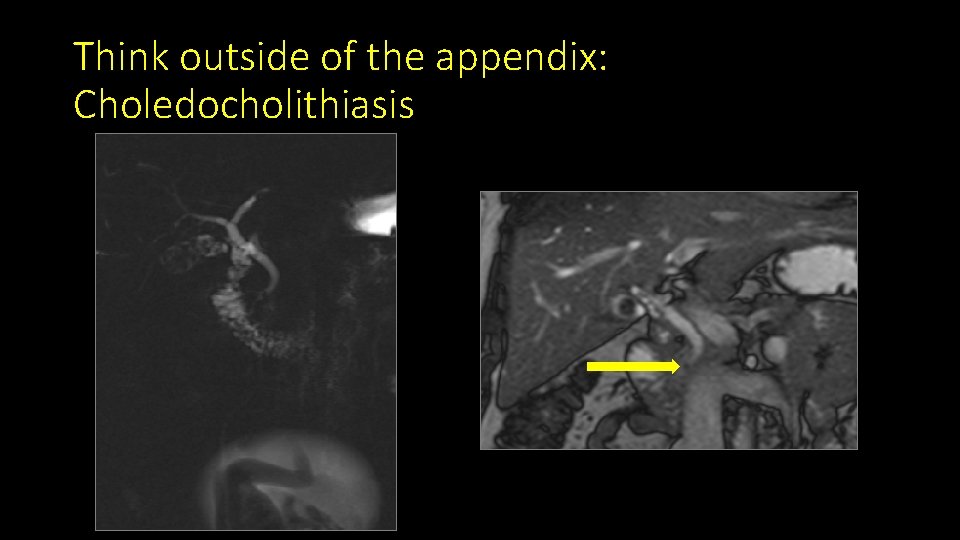

Think outside of the appendix: Choledocholithiasis